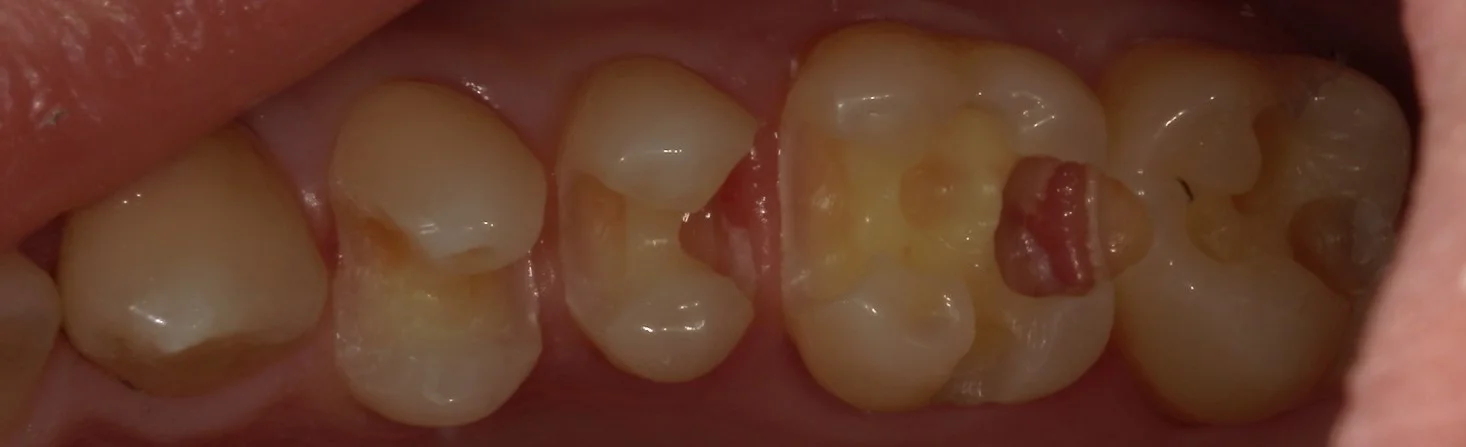

そして、金属と白い詰め物を外したのがこちら。

右から2番目については非常に真っ黒になっているのが分かりますね。

そして虫歯を取りきったのがこちらです。

中央2本が神経ギリギリの状態でした。

どちらも後ろ1/3~1/2は表層を残し、内面がほとんどすべてない状態になっています。

虫歯が歯茎よりも深い部分に入り込んでいました。

ここで歯茎を傷つけて出血させると、接着力が落ちてしまい、長期予後が期待できなくなってしまいますので気を付けて虫歯を取りきっていきます。